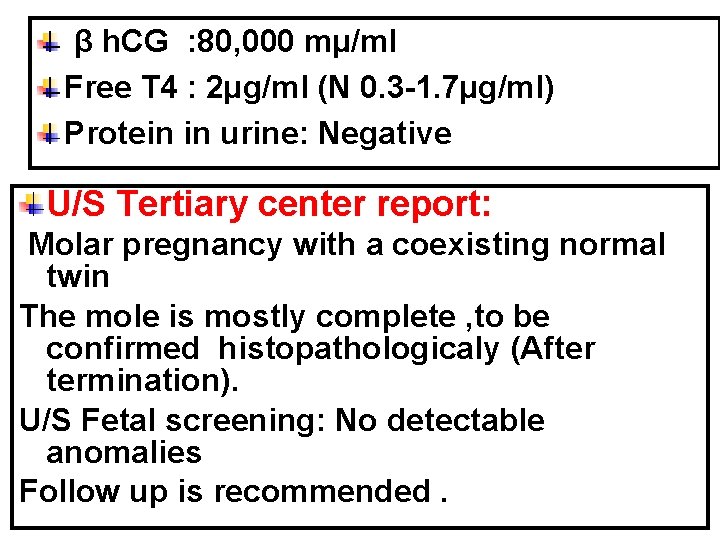

What Are The Required Investigations? Quantities serum β h. CG Free T 4 Protein in urine Rescanning after one week in a tertiary or fetal medicine center for diagnosis & screening.

β h. CG : 80, 000 mµ/ml Free T 4 : 2µg/ml (N 0. 3 -1. 7µg/ml) Protein in urine: Negative U/S Tertiary center report: Molar pregnancy with a coexisting normal twin The mole is mostly complete , to be confirmed histopathologicaly (After termination). U/S Fetal screening: No detectable anomalies Follow up is recommended.